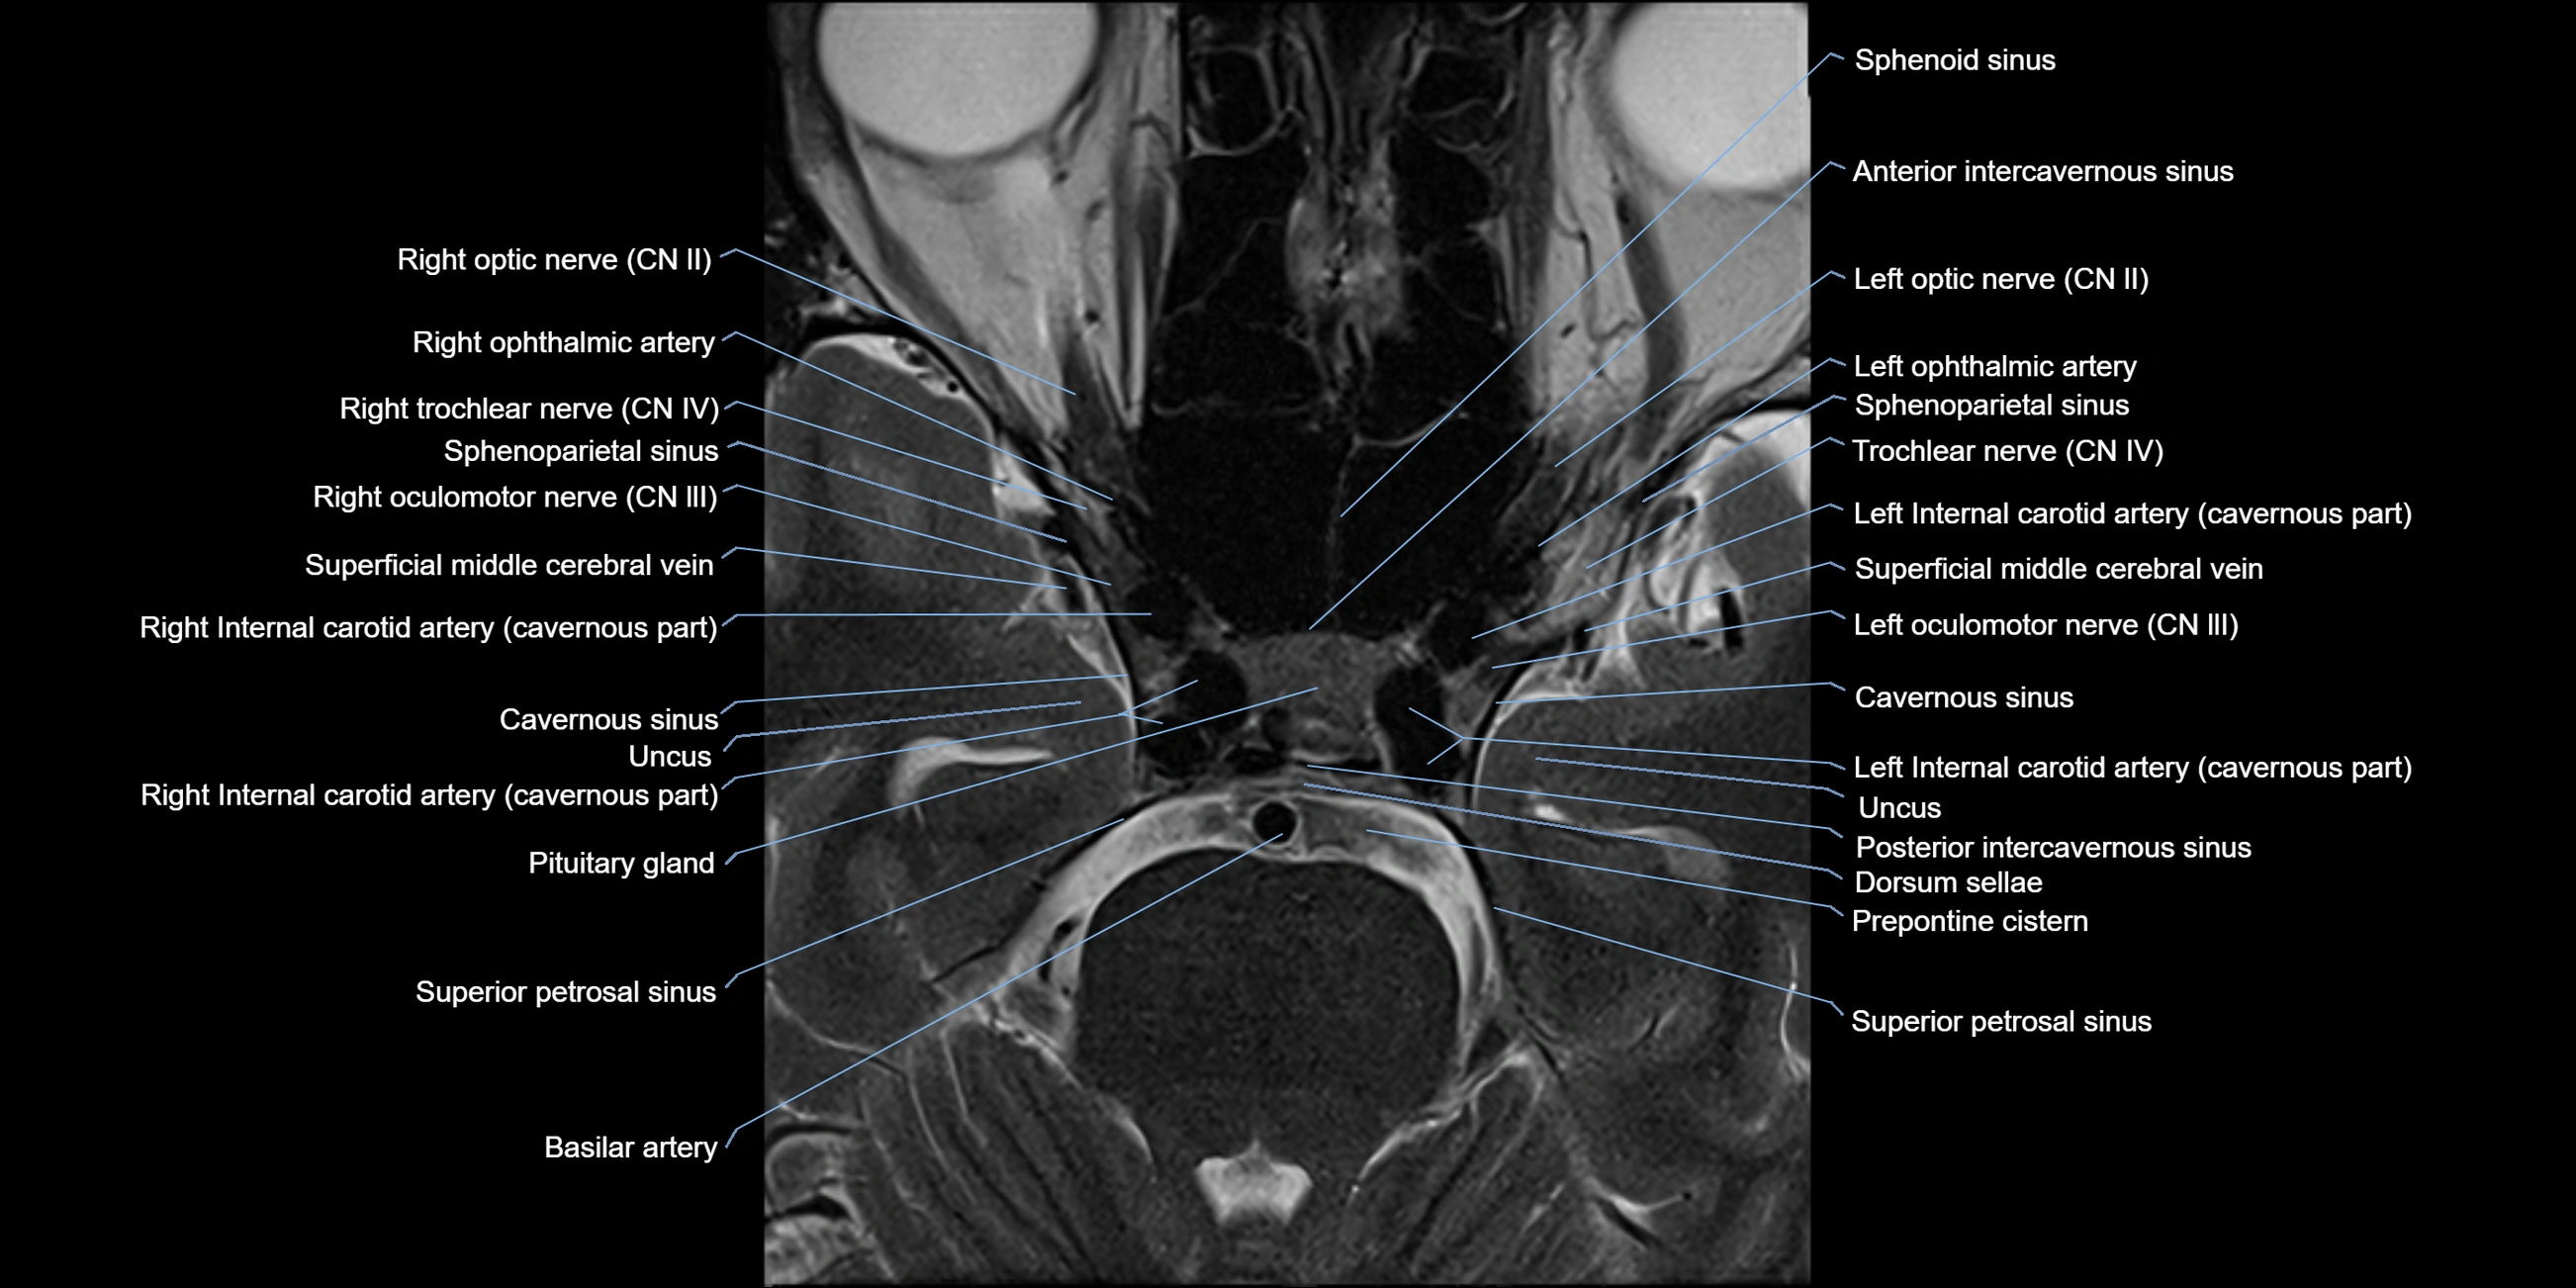

MRI images